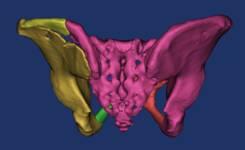

骨盆术前三维模型和模拟复位--正位后面观